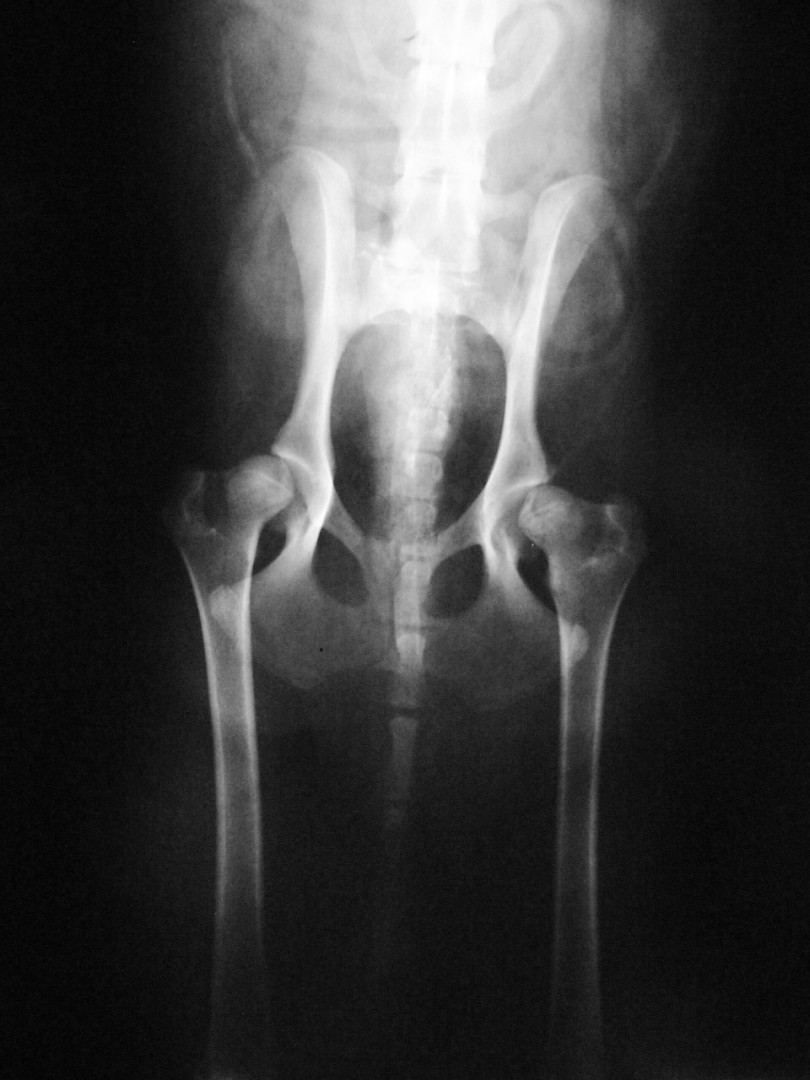

Teljes csípőízületi protézis

Bár a csípőízület megbetegedéseiről – mint a leggyakrabban tárgyalt ortopédiai megbetegedésről- első körben nem szerettem volna szólni, mégis megteszem, mert 2010. májusában egy hosszabb egyeztetést és szervezést követően beültettük az első teljes csípőízületi protézist…

Az első műtét remekül sikerült és Connor, a skót juhász kutya megkapta a bal oldali új csípőízületét. A 7 napi kórházi tartás is problémamentesen zajlott és a varratszedés idejére a műtött végtag terhelése gyakorlatilag hibátlan volt. Az 1 hónapos és a 3 hónapos kontroll RTG vizsgálatokon sem jelentkezett szövődményre utaló jel, az 1 éves postoperatív időszakban már csak az látszott, hogy a műtött lábát jobban terheli, mint a nem operált végtagot. Így 2011. júniusában – immár sokadik csípőízületi protézis műtétként- a jobb oldali csípőízületét is megoperáltuk. Connor gyakorlatilag azóta teljes életet él és vidáman játszik társaival, még birkákat is terel…A majd két éves, a protetizálás során szerzett tapasztalatok azonban nálunk is hozzák a szakirodalomban leírt szövődményi lehetőségeket és arányokat. Leggyakrabban a beültetett protézis ficamával találkoztunk, de akadt sajnos kilökődési reakció is. Ezen problémák – az előzetes tájékoztatás ellenére is- mindig váratlanul érik a tulajdonost és az állatorvost egyaránt. Megoldásuk szinte kizárólag műtéti, ami újabb kockázatot, újabb fizikai és anyagi áldozatot jelent.